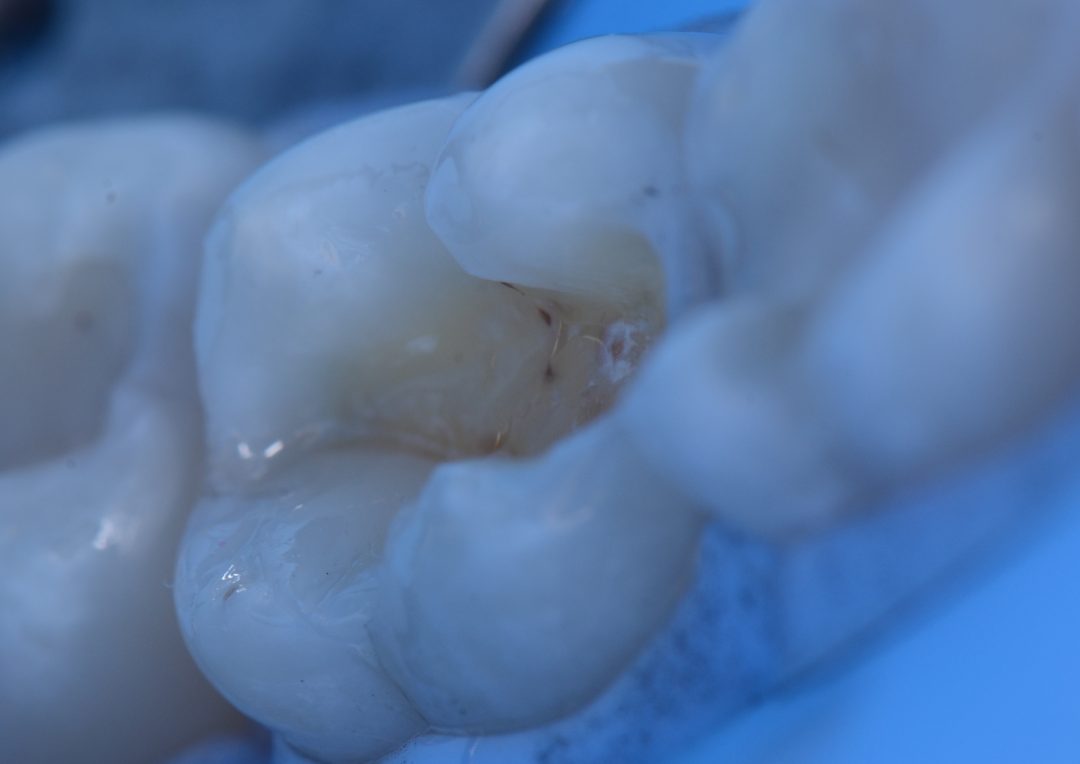

After anesthesia, absolute isolation and prophylaxis with pumice stone and water, the amalgam restoration on tooth 37 was removed. The cavosurface angle was carefully finished and etched with 37% phosphoric acid Condac 37 for 30 seconds, washed abundantly and the whole tooth, enamel and dentin, was dried with air.

Next, a first layer of Ambar Universal APS adhesive was applied actively with Cavibrush. Being it a universal adhesive system, it was applied using the self-etching technique since there is no removal of smear or mineral layer and, consequently, there is no exposition of collagen fibers. Therefore, following the self-etching technique, the dentine may and should be dried with air. Fifteen seconds after the first application, air spray was applied to evaporate the solvent and a second layer was applied in the same way and photoactivated.

Following that, the universal chroma composite Vittra APS Unique was applied in layers (since it is not a bulk-fill type composite) rebuilding the anatomy. This composite is very interesting because, in the beginning, before polymerization, the composite looks opaque and whitish. However, after photoactivation, the composite takes the color of the side walls of the tooth, integrating itself chromatically with the dental structure in a perfect way, allowing for the mimicking and a fantastic esthetic result, in a simple way, with just one composite. This new universal chroma composite came to revolutionize and, above all, simplify and facilitate, with extreme esthetic quality, restorative technique and procedures.